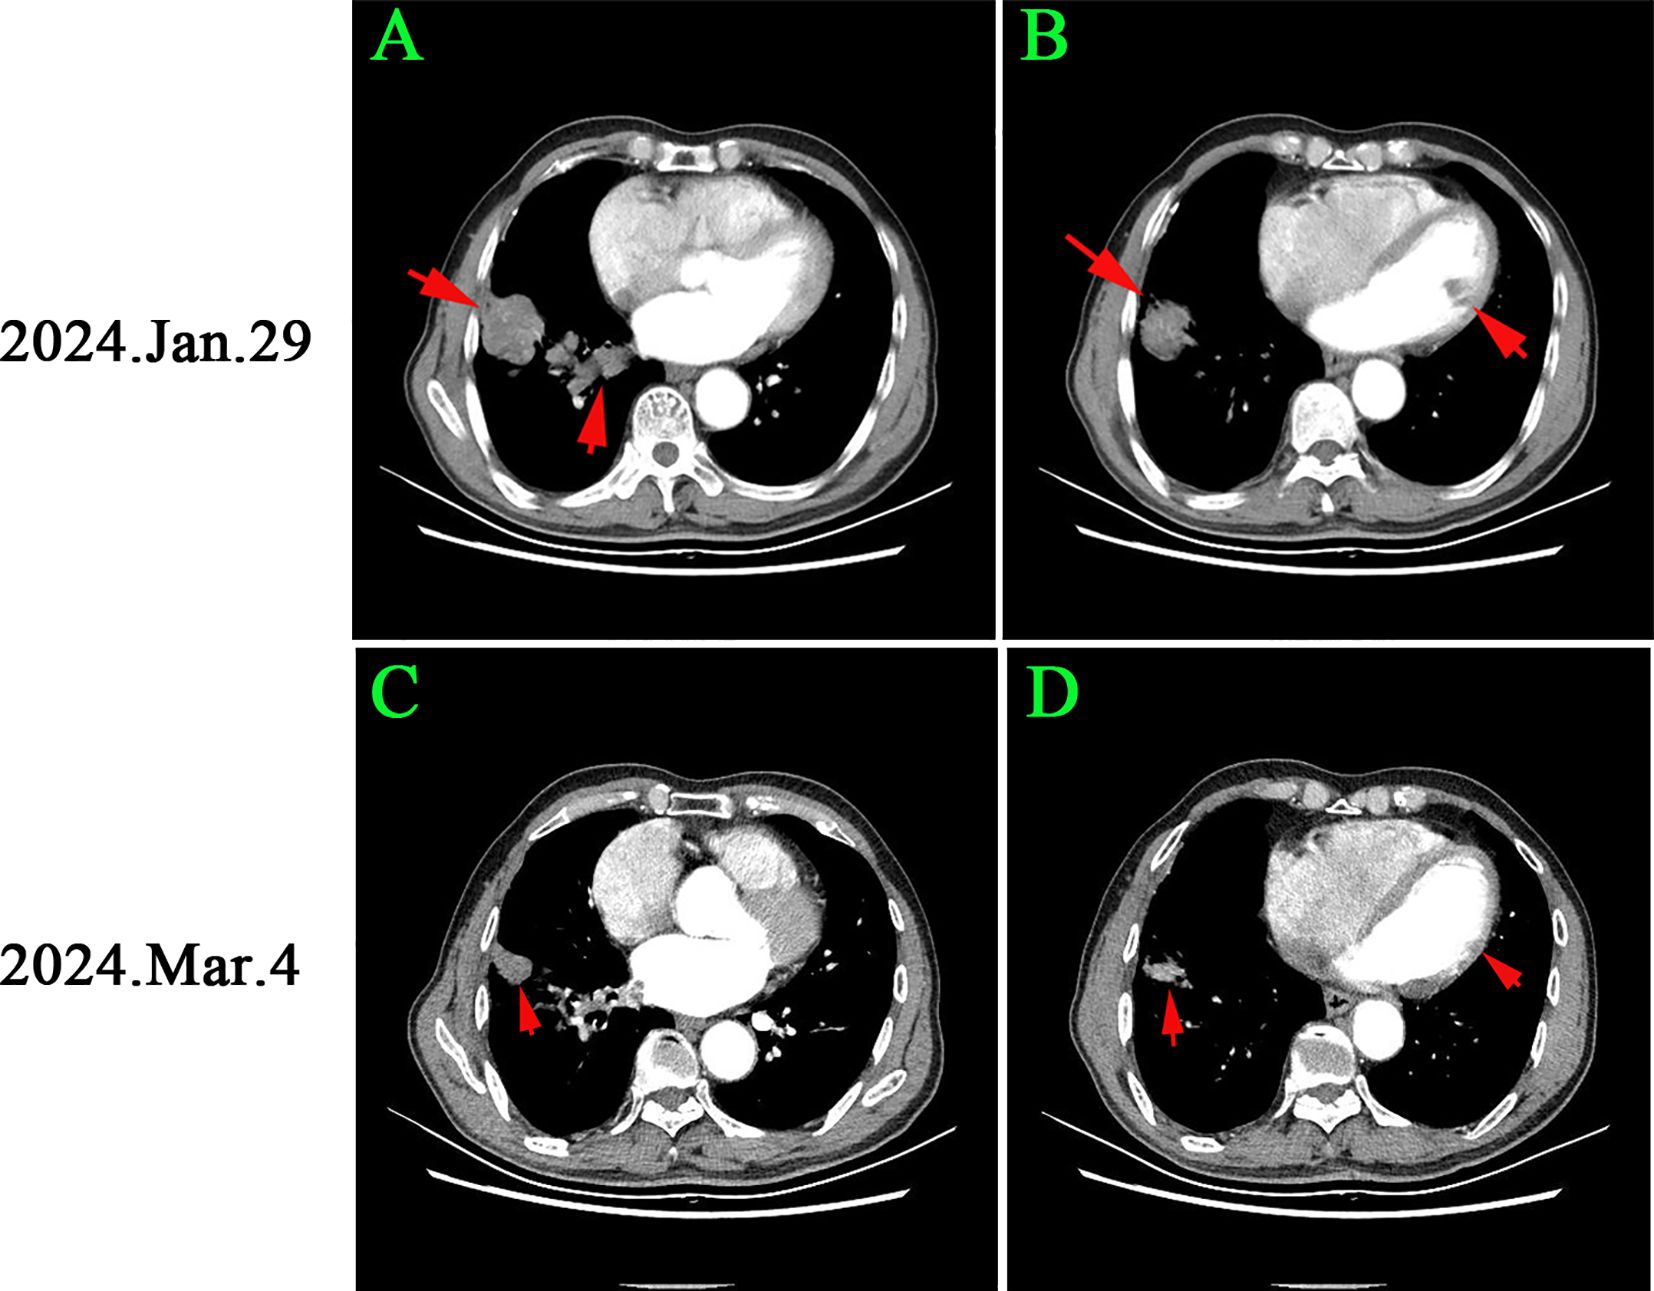

Thrombotic events represent a common complication and the second leading cause of mortality among patients with non-small cell lung cancer (NSCLC). Nonetheless, it is exceedingly rare for thrombosis to manifest initially in atypical locations, such as the popliteal artery, in individuals with NSCLC. In this report, we present a case involving an elderly patient with NSCLC who initially exhibited acute thrombosis of the popliteal artery in the left limb. The patient underwent a salvage arterial thrombectomy followed by a transfemoral amputation. Pathological examination revealed that the thrombus was a tumor embolus. A chest CT scan identified a mass in the right lower lung with a maximum diameter of 2.8 cm, along with multiple pulmonary nodules and a clot in the right inferior pulmonary vein. Pathological analysis of the lung mass confirmed the presence of lung adenocarcinoma, thereby verifying that the tumor embolus originated from NSCLC. The patient subsequently received treatment with osimertinib, resulting in partial remission. In instances of thrombosis occurring in uncommon sites, it is crucial to consider the potential for tumor thrombus.